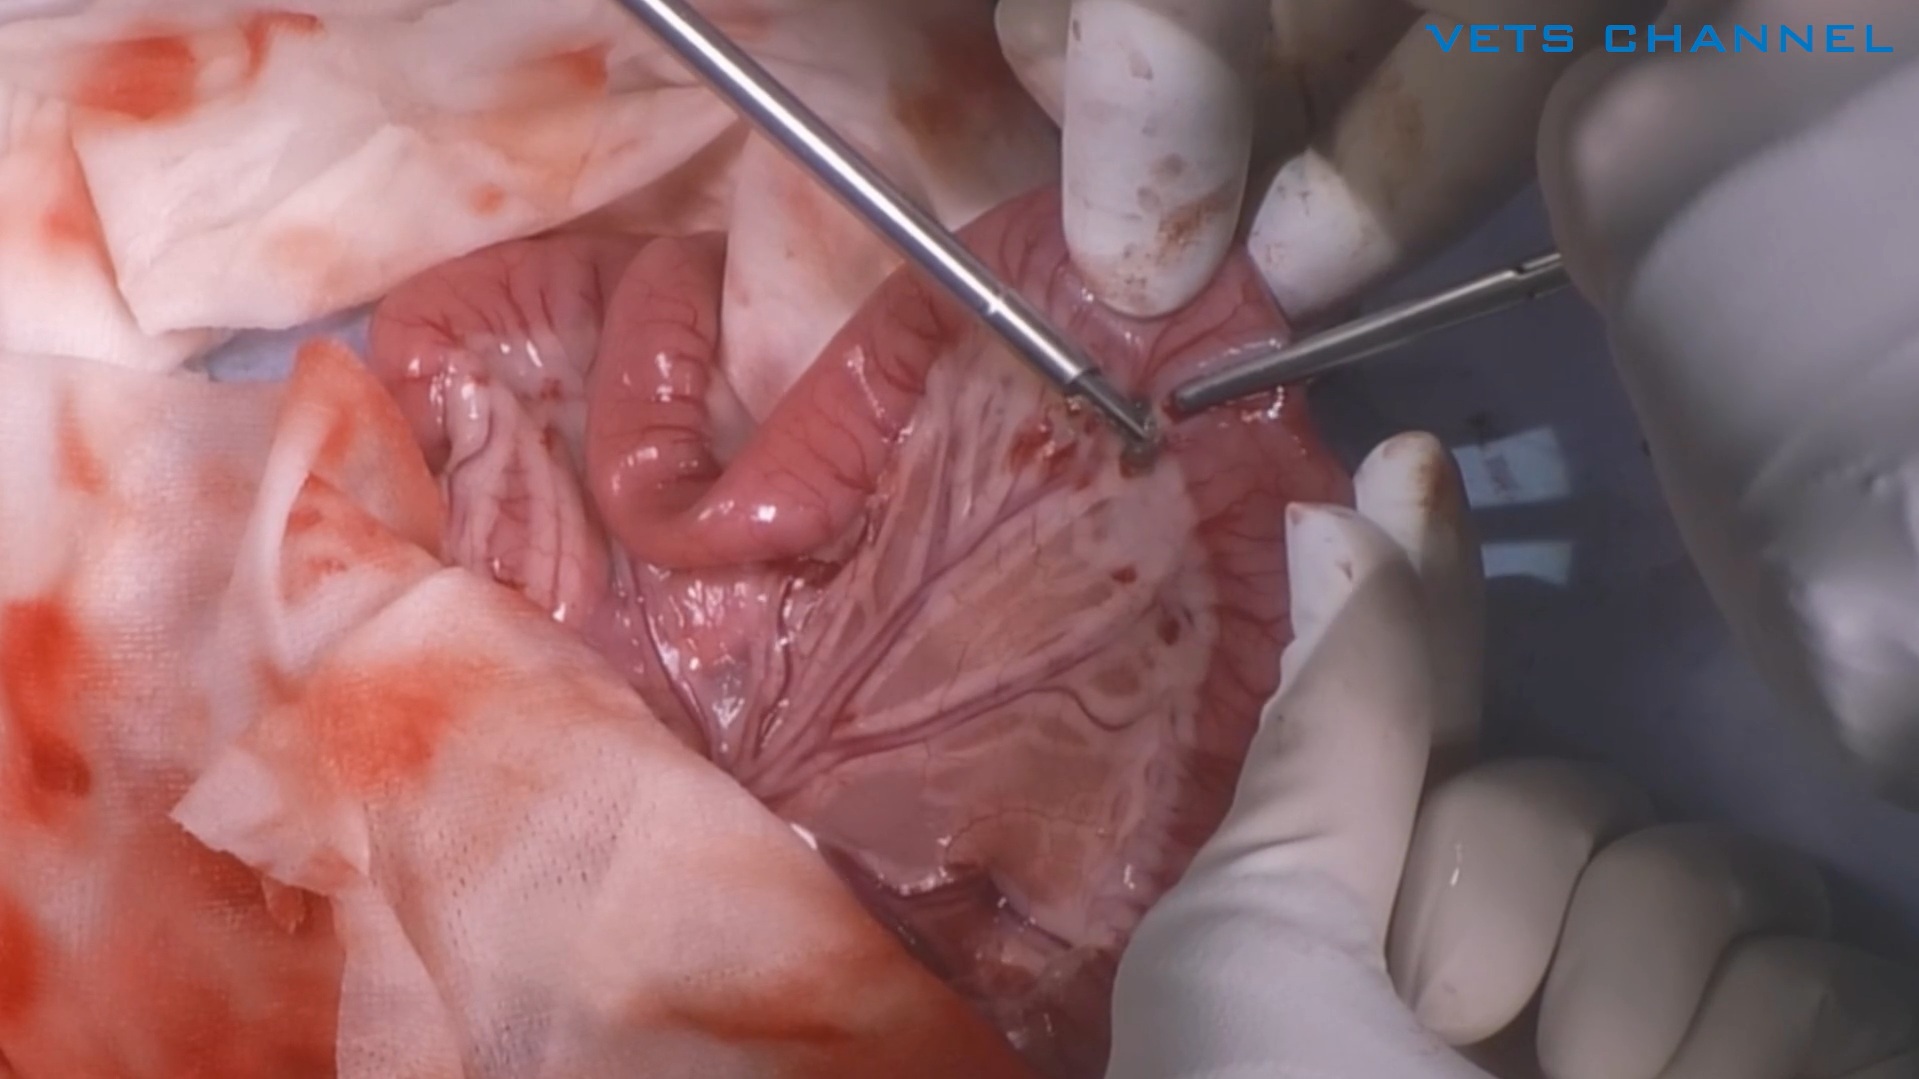

扁平上皮癌に対する上顎尾側切除術

- OPE

- 軟部外科

- 歯科・口腔外科

- 腫瘍科

- 犬

小材 祐介先生 (伊勢崎動物医療センター)

27分

2025/11/07

扁平上皮癌に対する上顎尾側切除術

- OPE

- 軟部外科

- 歯科・口腔外科

- 腫瘍科

- 犬

小材 祐介先生 (伊勢崎動物医療センター)

27分

2025/11/07

扁平上皮癌に対する上顎尾側切除術

- OPE

- 軟部外科

- 歯科・口腔外科

- 腫瘍科

- 犬

小材 祐介先生 (伊勢崎動物医療センター)

27分

2025/11/07